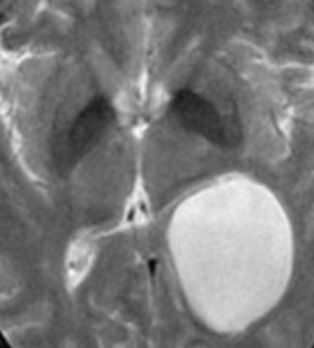

МРТ головного мозга. Т1-взвешенные корональная и сагиттальная МРТ. Эпидермоидная киста левой височной доли.

При МРТ головного мозга картина неспецифическая и зависит от содержимого кисты. Если она не содержит жира, то имеет ликворную интенсивность сигнала . В таком случае эпидермоидная киста трудно отличима от арахноидальной, хотя, как правило, не столь однородная. На МРТ типа FLAIR и диффузионно-взвешенных МРТ изображениях содержимое эпидермоидов светлее ликворного. Жировое содержимое, такие эпидермоиды еще называют холестеатомой, приводит к высокому сигналу на Т1-взвешенных МРТ головного мозга. Видимо, он обусловлен липидами, но не холестеролом. На Т2-взвешенных МРТ головного мозга он менее интенсивен чем ликвор. Контуры эпидермоидов всегда четкие. Холестеатомы составляют всего 3-5% от эпидермоидов. В 15-20% случаев встречается кальцификация по переферии кисты. Редко наблюдается контрастирование стенок.

При МРТ головного мозга картина неспецифическая и зависит от содержимого кисты. Если она не содержит жира, топри МРТ головного мозга эпидермоидная киста имеет ликворную интенсивность сигнала. В таком случае эпидермоидная киста трудно отличима от арахноидальной, хотя, как правило, не столь однородная. На FLAIR томограммах и диффузионно-взвешенных МРТ головного мозга содержимое эпидермоидов светлее ликворного. Жировое содержимое, такие эпидермоиды еще называют холестеатомой, приводит к высокому сигналу на Т1-зависимых МРТ головного мозга. Видимо, он обусловлен липидами, но не холестеролом. На Т2-взвешенных МРТ головного мозга он менее интенсивен чем ликвор. Контуры эпидермоидов на МРТ всегда четкие. Холестеатомы составляют всего 3-5% от эпидермоидов. В 15-20% случаев встречается кальцификация по переферии кисты. Редко наблюдается усиление стенок кисты при МРТ головного мозга с контрастированием.